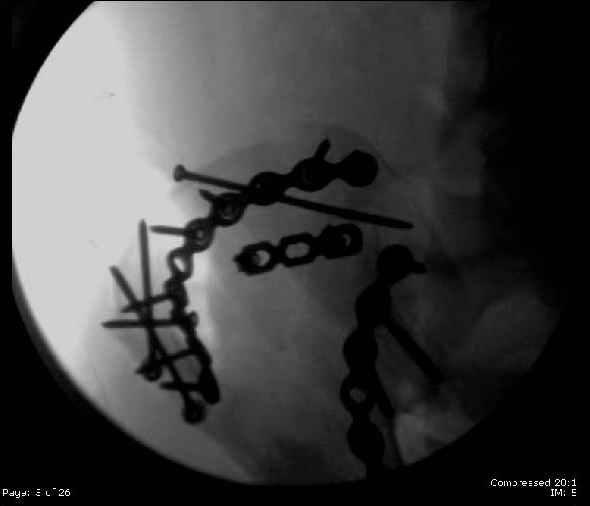

Here are the postop fluoros.

Reduced the triangular wedge piece of iliac wing to posterior intact ilium (crescent), held w/k-wire, then used 3-hole push plate to keep from moving, lagged from lat-med w 3.5 screw.

Then 6-hole plate along brim with 1 screw in R sacral ala. Then lagged 2 screws along crest A --> P. finally 10-hole plate along inner aspect of crest. R posterior ilium still a bit stepped off.

PS - as for the femur -- I had an idea about the malreduction in flexion, varus & ext rotation after seeing my colleague's postop fluoros from the nailing. I first recognized the actual magnitude of the malrotation after transferring the pt to the OR table for ORIF of his pelvis, and did not have consent for revision, among other

issues. I've since spoken with the first surgeon (who did the femur nailing) and we will address that, probably together, ASAP, but before the pt leaves the hospital.